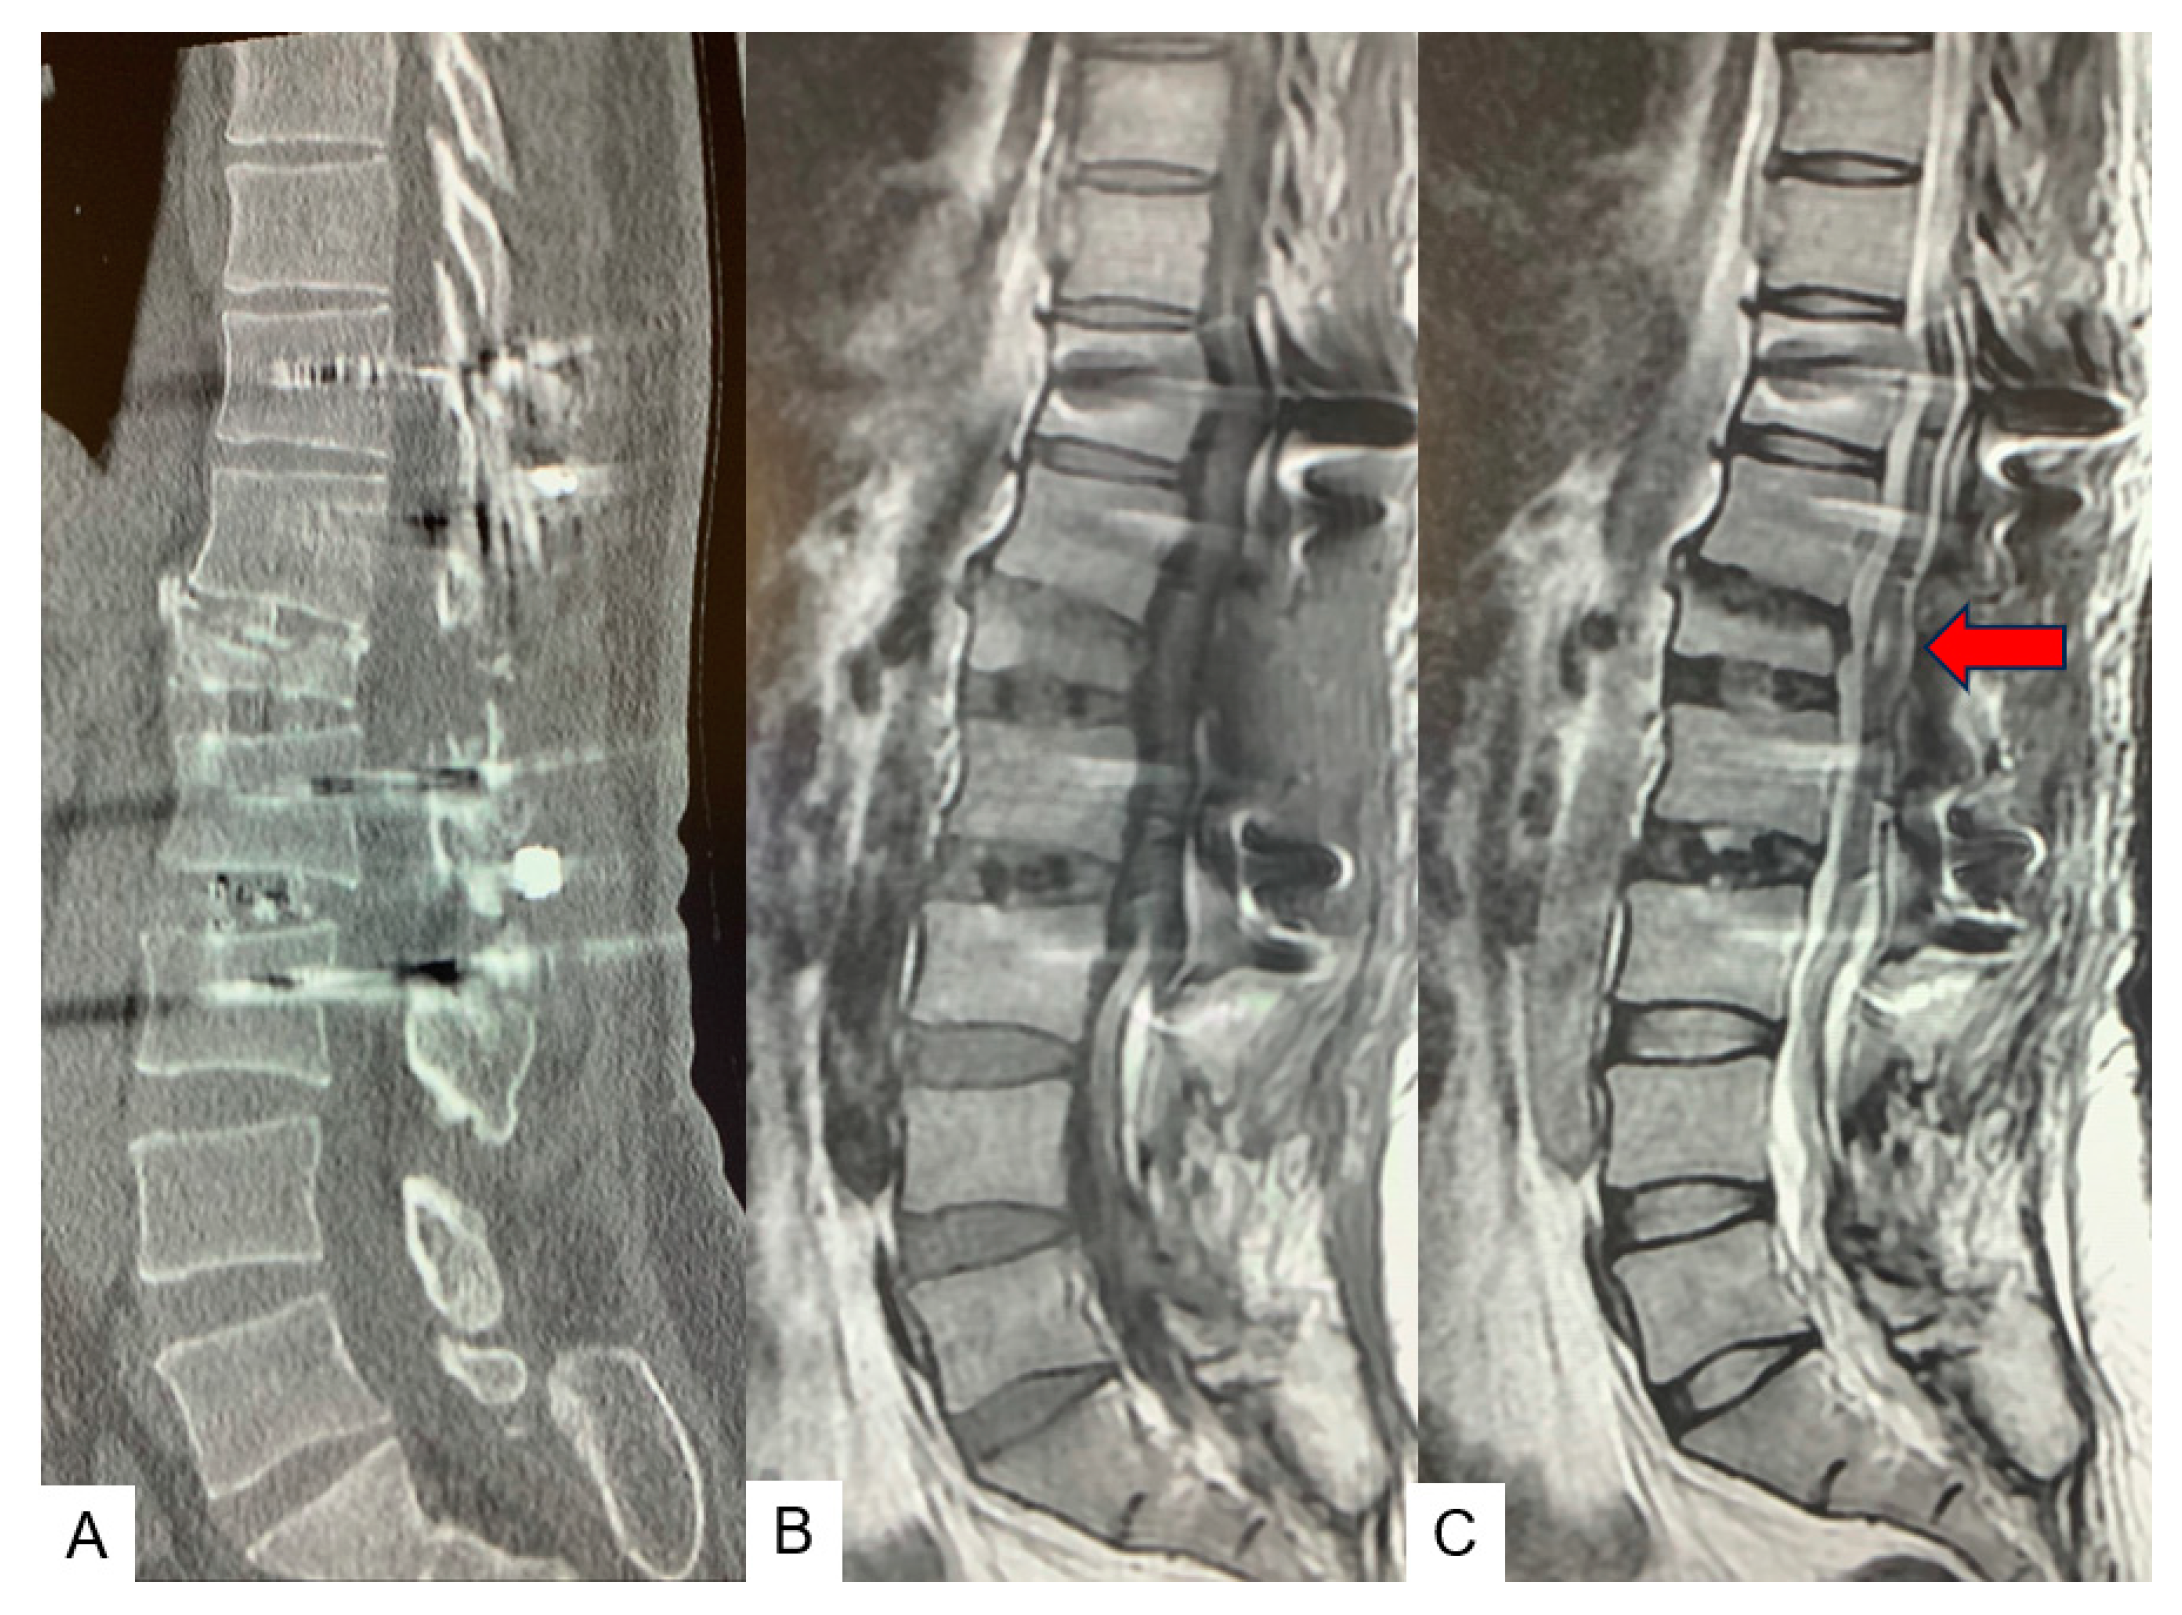

2.3. Preoperative Imaging

2.4. Surgery

2.4.1. Anterior Discectomy

2.4.2. Posterior Osteotomy

2.5. Postoperative Images